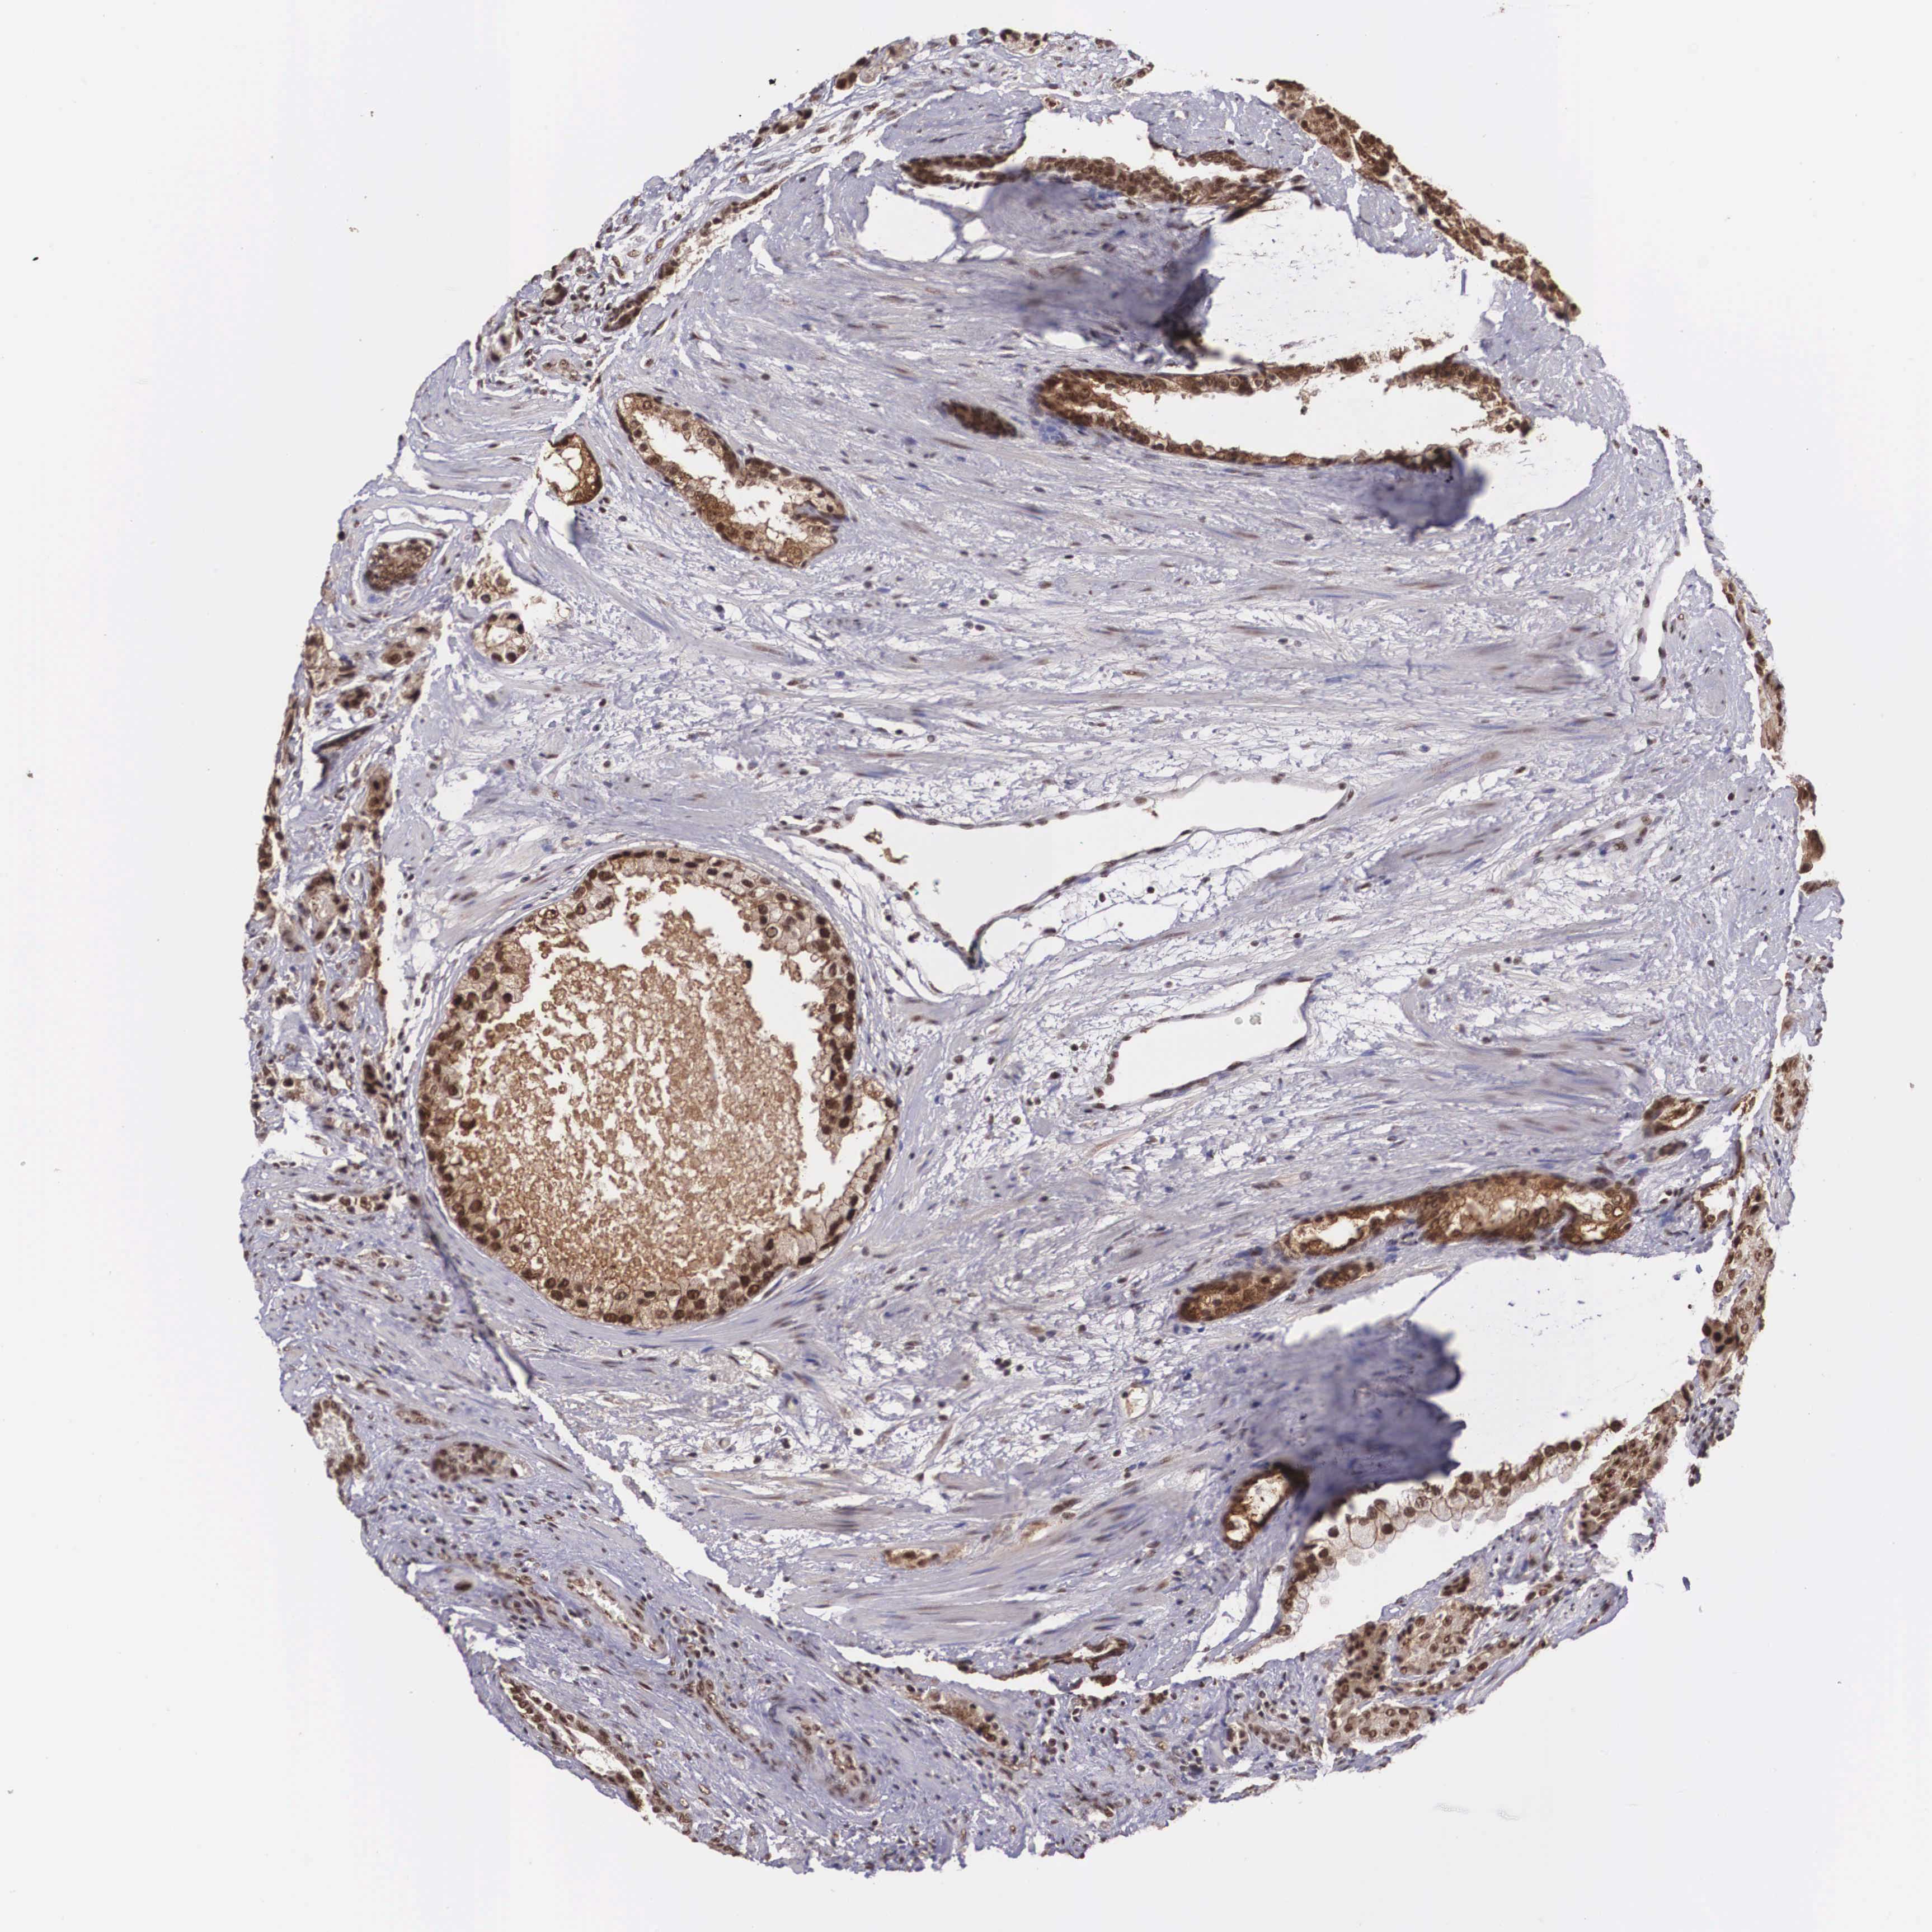

PROSTATE CANCER - Protein expressioni

A mouse-over function shows sample information and annotation data. Click on an image to view it in a full screen mode. Samples can be filtered based on level of antibody staining by selecting one or several of the following categories: high, medium, low and not detected. The assay and annotation is described here.

Antibody stainingi

Antibody staining in the annotated cell types in the current human tissue is reported as not detected, low, medium, or high, based on conventional immunohistochemistry profiling in selected tissues. This score is based on the combination of the staining intensity and fraction of stained cells.

Each image is clickable and will lead to virtual microscopy that enables deeper exploration of all samples and also displays staining intensity scores, fraction scores and subcellular localization as well as patient and tissue information for each sample.

Antibody HPA000827

Adenocarcinoma, Medium grade

Adenocarcinoma, Low grade

Adenocarcinoma, High grade